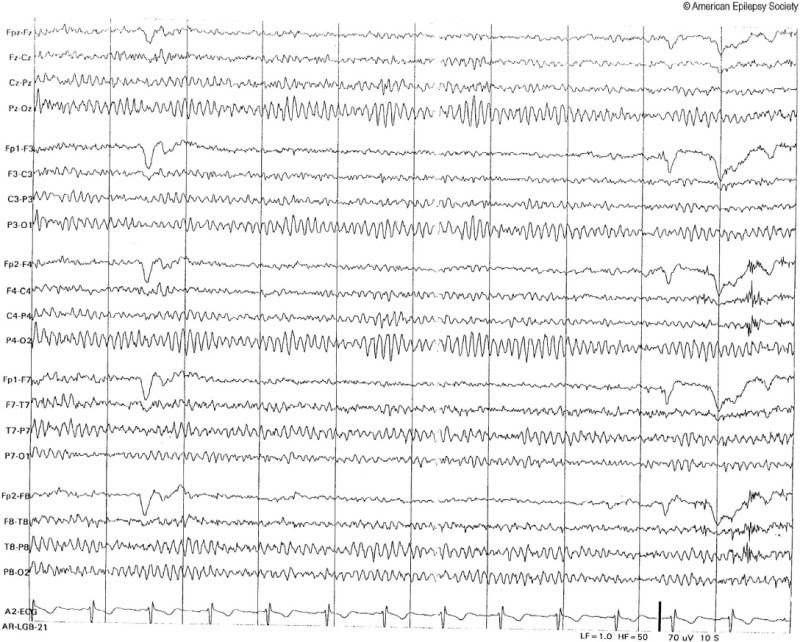

So is the image above normal or abnormal? It looks like quite a mess of jumbled lines, but we can't use that standard to decide. Take for example, the image below from a more common test called an electroencephalogram, or EEG. It also looks like a mess of random squiggling lines...

But it just so happens that this is a completely normal EEG, so clearly there's a bit more to making abnormal test results obvious for an untrained eye (like a patient, attorney, or insurance adjuster) than just showing the image on it's own.